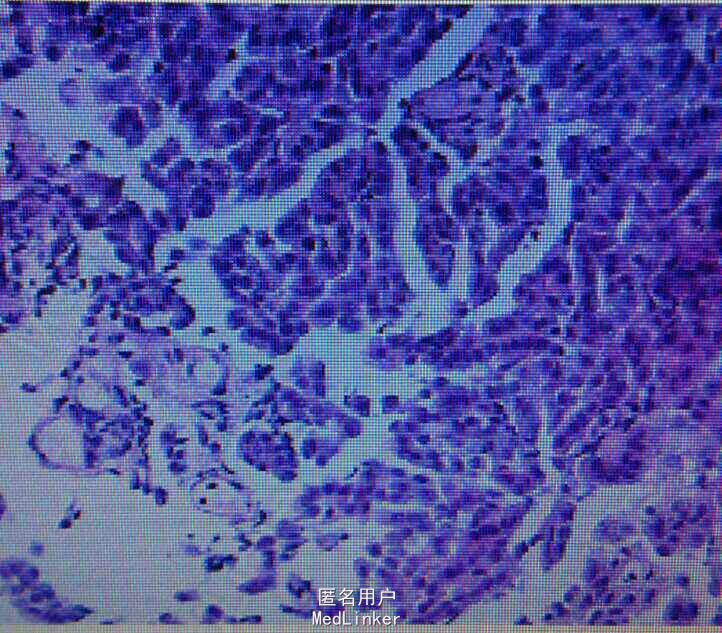

查体右下肺呼吸音减弱,无干湿罗音。心音正常。胸片示右胸膜增厚,少量积液。行胸膜活检示胸膜恶性间皮瘤。